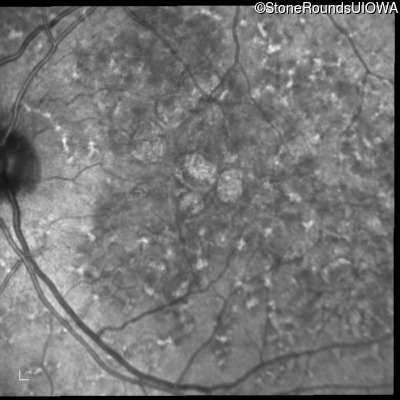

Blue Autofluorescence - Right - 20/20 -1 sc

Exemplar